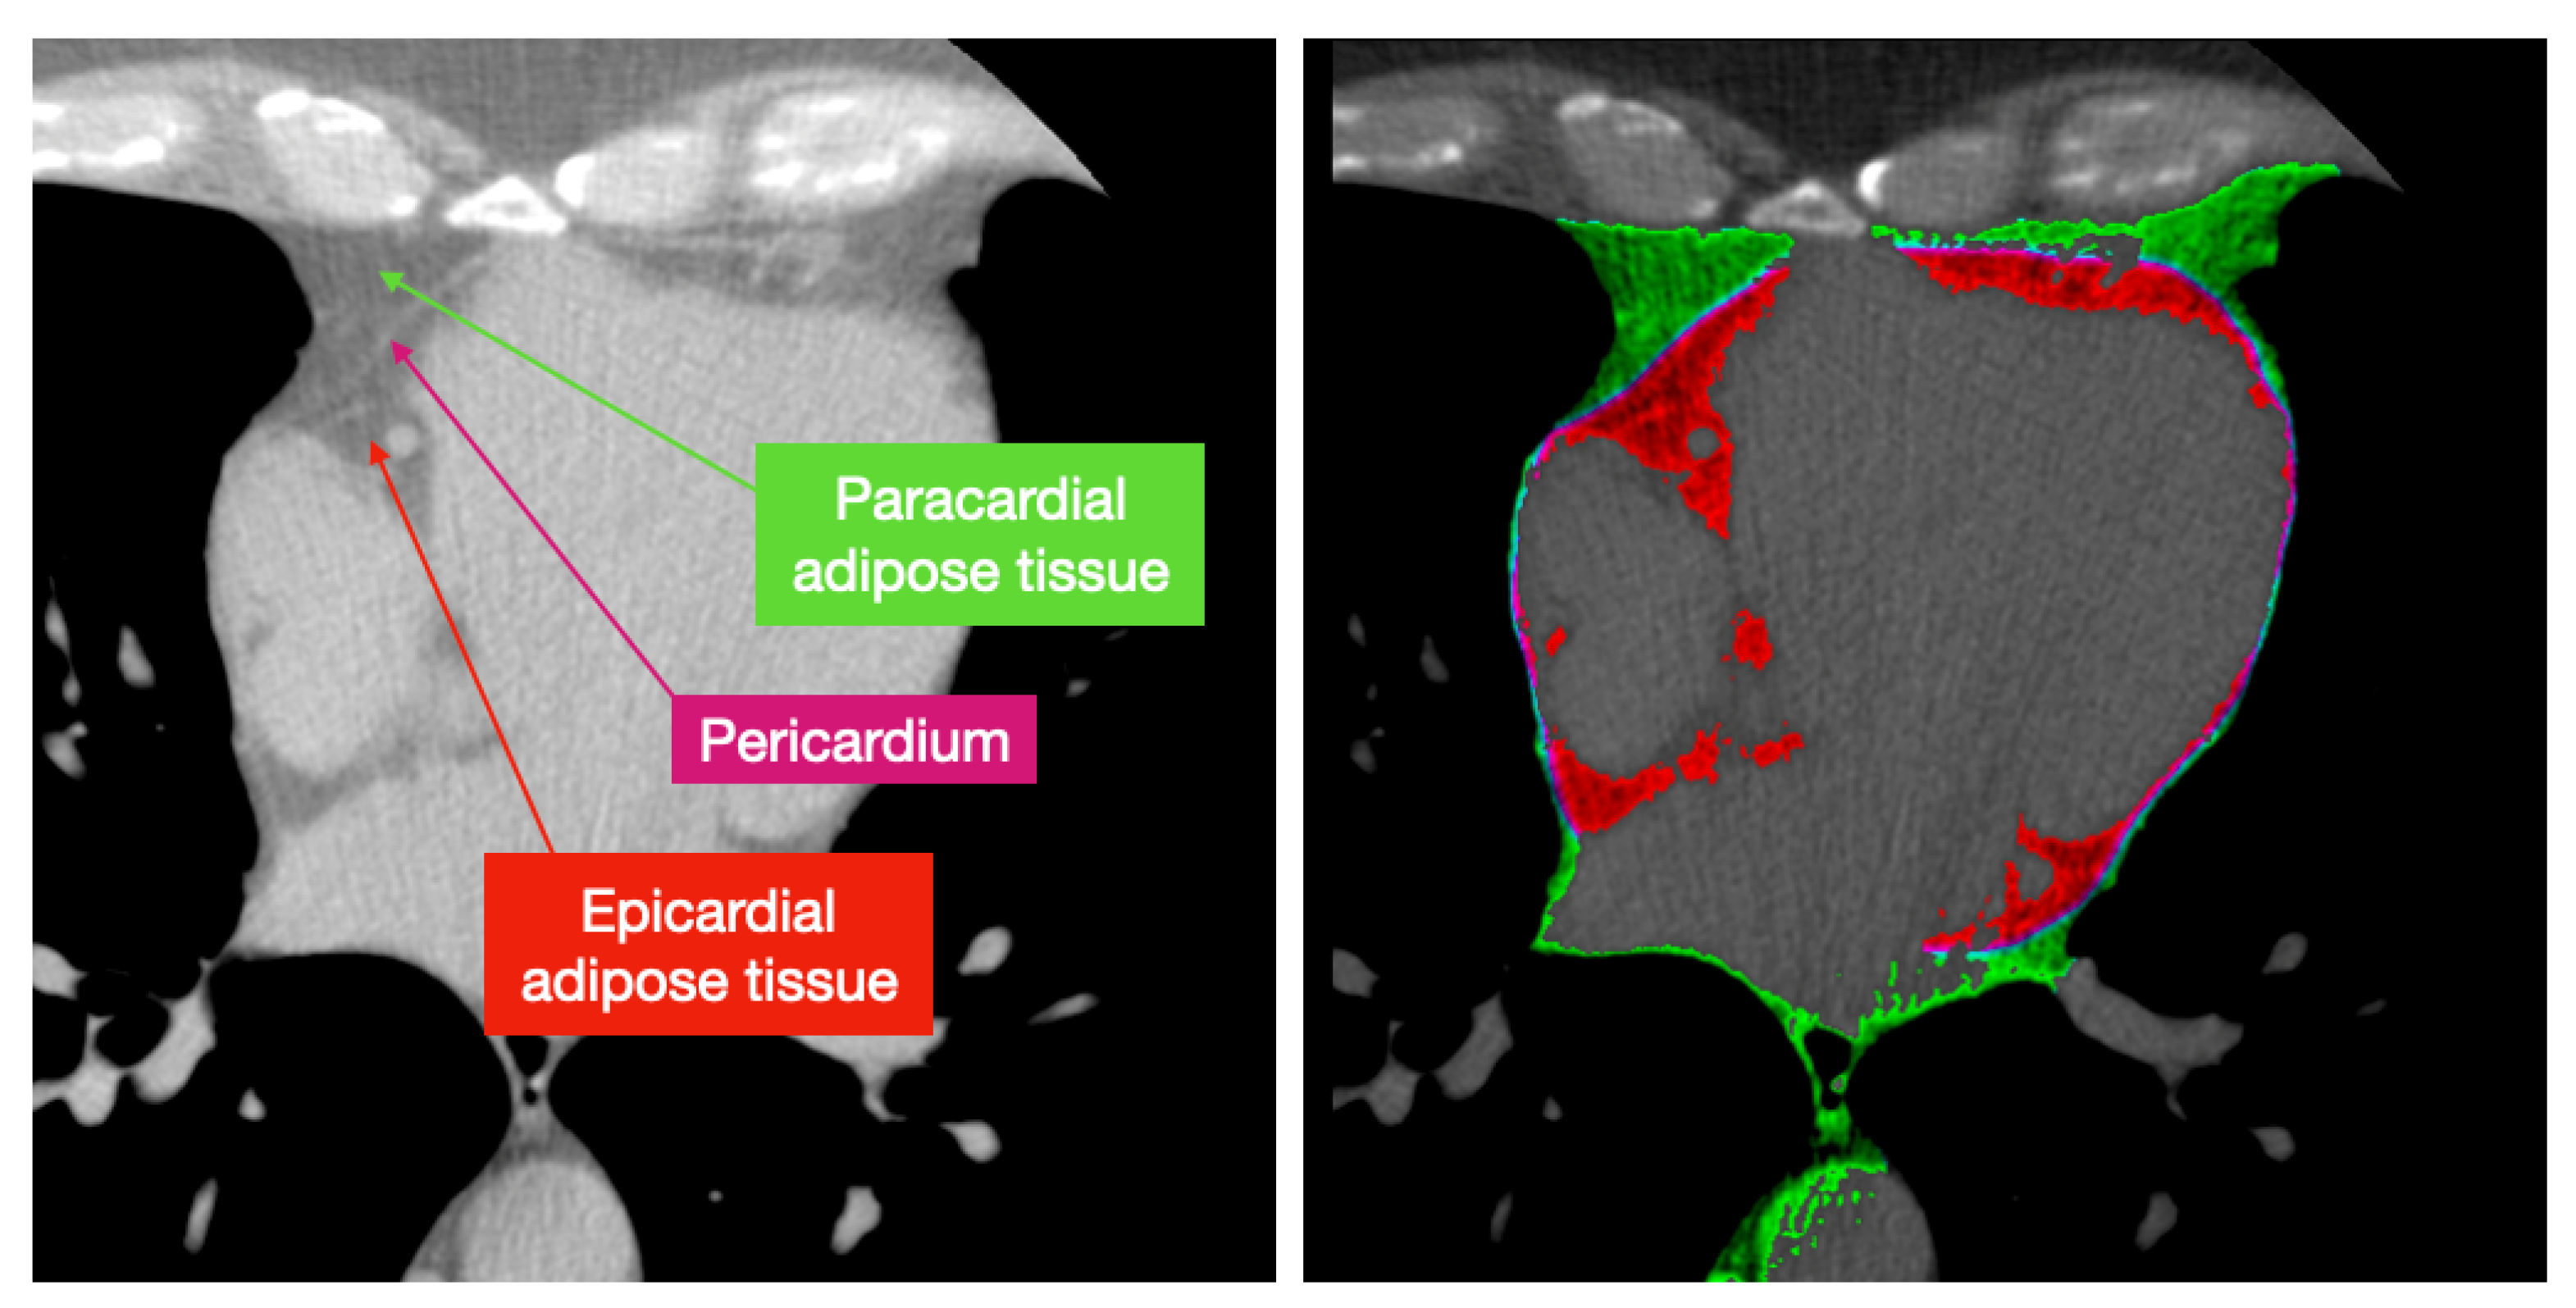

Epicardial adipose tissue is most loosely defined as any adipose tissue within the pericardial sac. The fat immediately outside the pericardial sac is called paracardial fat, and together they form pericardial fat [6,21]. Epicardial fat is mostly concentrated in the atrioventricular and interventricular grooves and along the major branches of the coronary arteries and around the atria Sacks and Fain [10]. Paracardial fat is concentrated on the outside of the parietal pericardium within the mediastinum.

It should be noted that there are disagreements in the medical literature on the terminology and anatomical definitions of cardiac adipose tissues. Namely, pericardial fat is sometimes referred to as intrathoracic fat [6] and EAT and PAT are sometimes separated as two disjoint tissues and not a subset of each other [16,21]. It can be difficult to compare methods of EAT and PAT quantification since the used definitions can vary the quantified volume. In this review, we took that into account and analyzed the definitions used by each mentioned paper to make sure a valid comparison is made. In the rest of the paper we adopt the following definitions, according to the definitions most commonly used in the analyzed literature:

• Epicardial adipose tissue is all adipose tissue enclosed by the pericardium.

• Paracardial adipose tissue lies just outside the pericardium.

• The union of these tissues is pericardial adipose tissue.